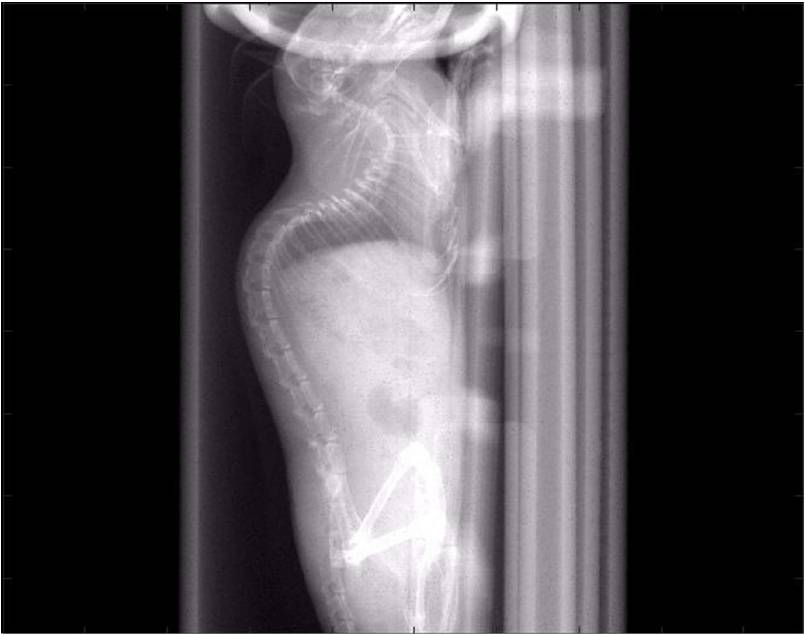

檢測案例

小鼠股骨

超高分辨率模式下像素大小為9μm。

A軸向和矢狀面顯示小鼠股骨結(jié)構(gòu)。

B用鈦材料植入的穿過骨頭的冠狀切片